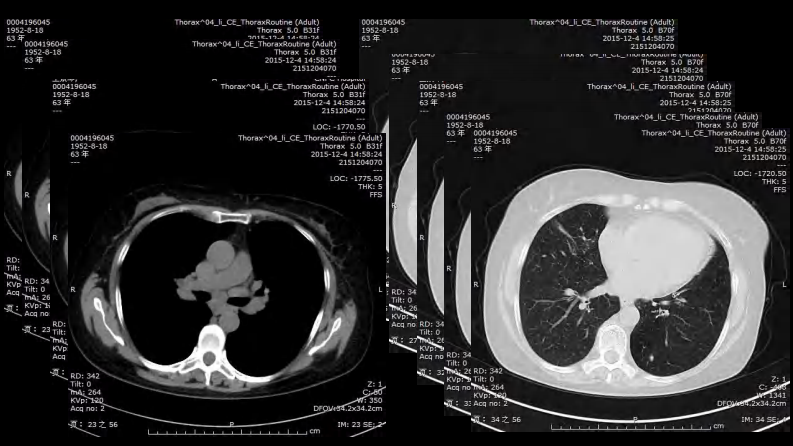

胸部结节病综合影像学交流.pdf